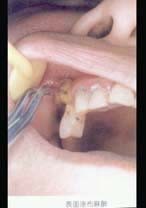

口腔外科學(A1/A2型題4)

一、A型題:每一道考試題下面有A、B、C、D、E五個備選答案。請從中選擇一個最佳答案。

4.患者下頜6根尖部有一瘺孔,有少許膿汁,扣診(-),無齲壞,不松動。下頜8低位阻生,冠周組織輕度紅赤不腫。診斷首先應考慮是  (    )

正確答案:D